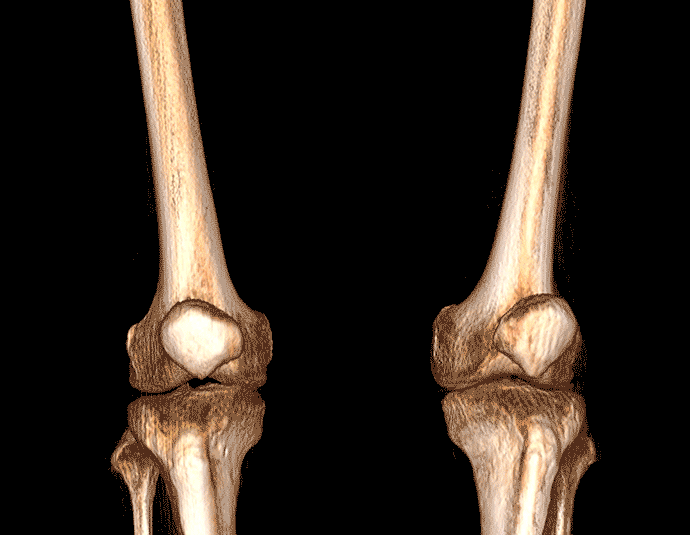

独特的负重位三维影像

填补常规CT/MR空白

助力术前规划和术后评估

• 膝关节

VR体绘制重建